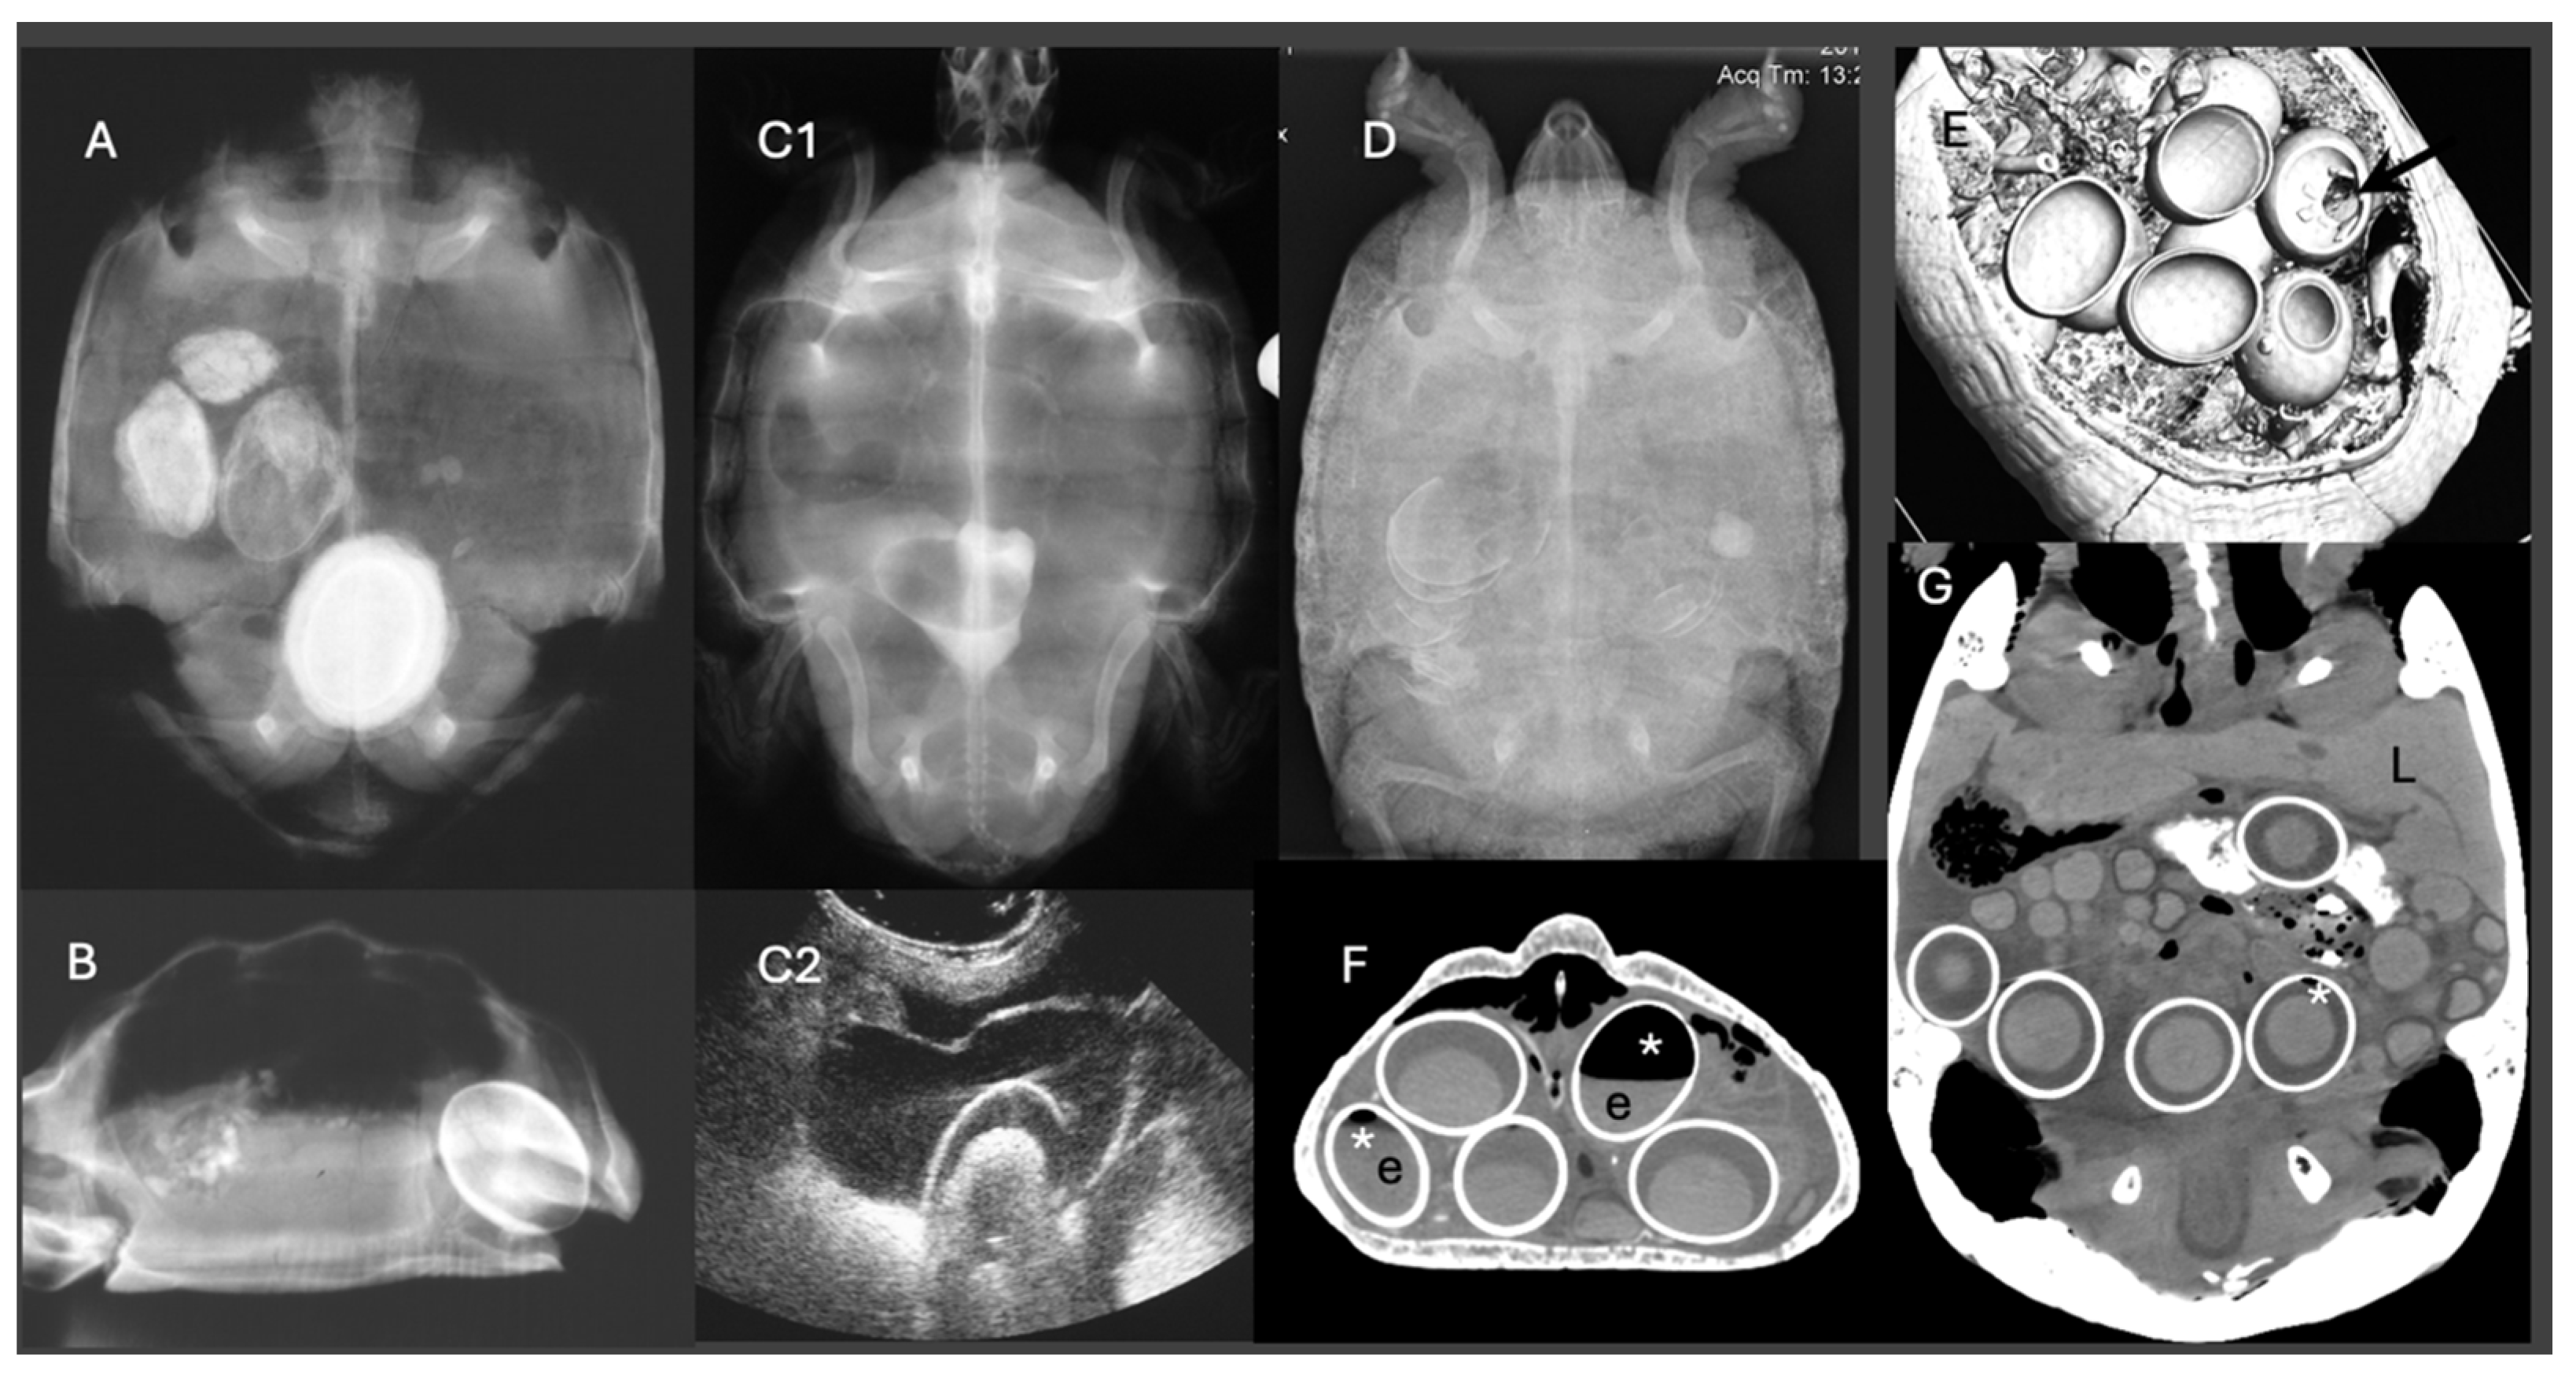

Dystocia, or egg-binding, is a common reproductive emergency in reptiles, often arising from multifactorial systemic and environmental causes. This review focuses on the biochemical and hepatic determinants contributing to dystocia across major reptilian taxa, including lizards, snakes, and chelonians. Prolonged vitellogenesis, hepatic lipidosis, and metabolic disturbances such as hypocalcemia or elevated bile acids may impair oviductal contractility and egg passage, increasing the risk of reproductive failure. The pathophysiology of dystocia is examined with particular emphasis on liver function and its role in reproductive hormone metabolism, nutrient allocation, and systemic homeostasis. Diagnostic strategies, ranging from radiography and ultrasonography to plasma biochemistry, are evaluated for their relevance in assessing reproductive status and perioperative risk. Management options, including medical interventions (e.g., oxytocin protocols, supportive therapy) and surgical techniques (e.g., ovocentesis, coeliotomy, ovariosalpingectomy), are reviewed with consideration of anesthetic safety in metabolically compromised patients. This review aims to inform clinical decision-making by integrating diagnostic and therapeutic approaches with a strong emphasis on hepatic function and biochemical indicators, thereby improving outcomes in the veterinary management of reproductive failure in reptiles.

Dystocia represents a multifactorial and clinically significant reproductive disorder affecting a broad spectrum of reptilian species. Commonly resulting from prolonged vitellogenesis, endocrine disruption, or hepatic lipidosis, dystocia is often exacerbated by suboptimal husbandry or concurrent disease. This review critically evaluates the etiology, diagnostic criteria, and therapeutic interventions associated with this condition. Emphasis is placed on the interplay between metabolic exhaustion and hepatic compromise, which may lower the threshold for surgical intervention. The efficacy and limitations of oxytocin-based protocols are discussed in the context of hormonal receptor variability and response attenuation. Advanced diagnostic modalities, including ultrasonography, radiography/CT, and biochemical profiling, are reviewed for their utility in case stratification. Finally, surgical management options are considered for cases refractory to medical treatment, with attention paid to timing, anesthetic risk, and post-operative care. Collectively, this synthesis aims to inform evidence-based clinical decision-making and promote improved standards of care in reptile reproductive medicine.